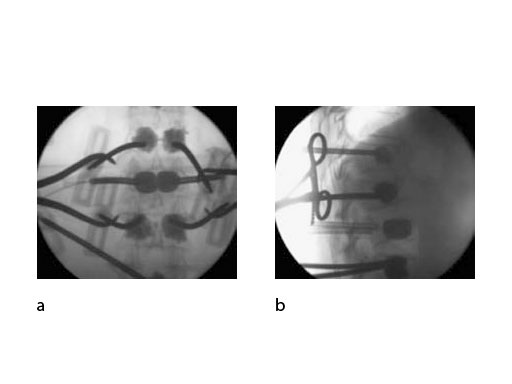

The optimized balloon stiffness allows for well controlled inflation and optimized lifting efficacy, reducing the risk of the balloon following the path of least resistance. Moreover, 2 radiopaque markers help in the x-ray visualization of the balloon to facilitate accurate placement (Fig 5).

The controlled inflation of the balloons allows you to reduce the fracture and create a cavity in the cancellous bone. This containment can subsequently be filled using a legally-marketed bone filler adequately indicated for kyphoplasty and/or vertebroplasty procedures, to stabilize fractures in the vertebral body, prevent further collapse of the vertebra, and to reduce pain (Fig 6). The direction of the bone filler flow can be changed by orienteering the handle of the injection needle with the side opening.